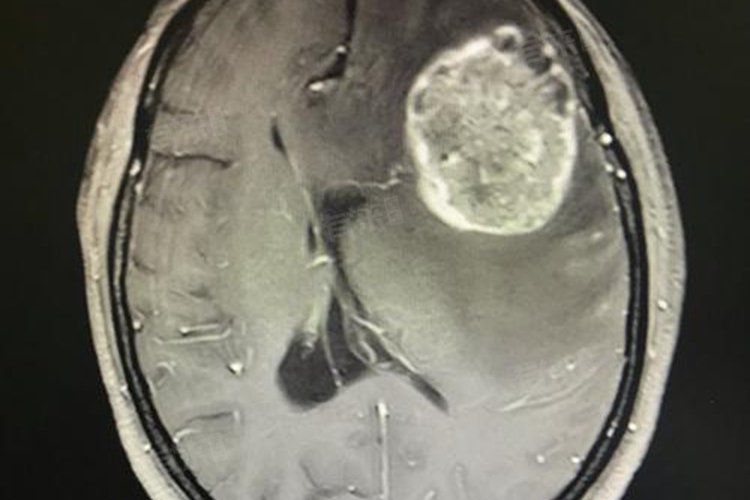

- 如果病理报告指出肿块是由炎症、感染或其他非恶性原因引起的,则这被认为是良性的。但如果病理学证实了淋巴细胞的恶性转化,则被归类为淋巴瘤,属于恶性肿瘤。若肿瘤的恶性程度较高,存活期可能只有2-3周,若肿瘤的恶性程度较低,可能会有6-10个月的存活期。

- 如果癌症扩散到肝脏、肺脏等重要内脏部位,且扩散范围较广,患者的生存时间可能会更短。患者对放化疗、靶向药物或免疫药物等治疗的反应也会影响生存期。如果治疗有效,能够控制癌症的扩散,患者的生存期可能会延长。